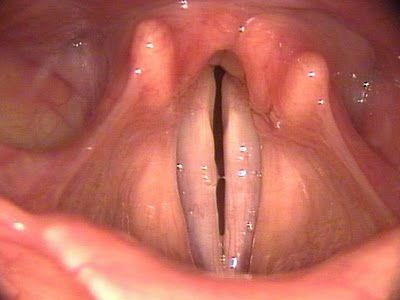

- Двофазний — дихання дзвінке, висока тоном, шумне. Уражену ділянку — на рівні голосових складок.

Якщо голосові зв’язки «нерухомі» необхідно термінове втручання